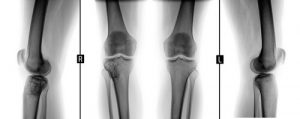

- Рентгенография.

- КТ, МРТ или ПЭТ-КТ.